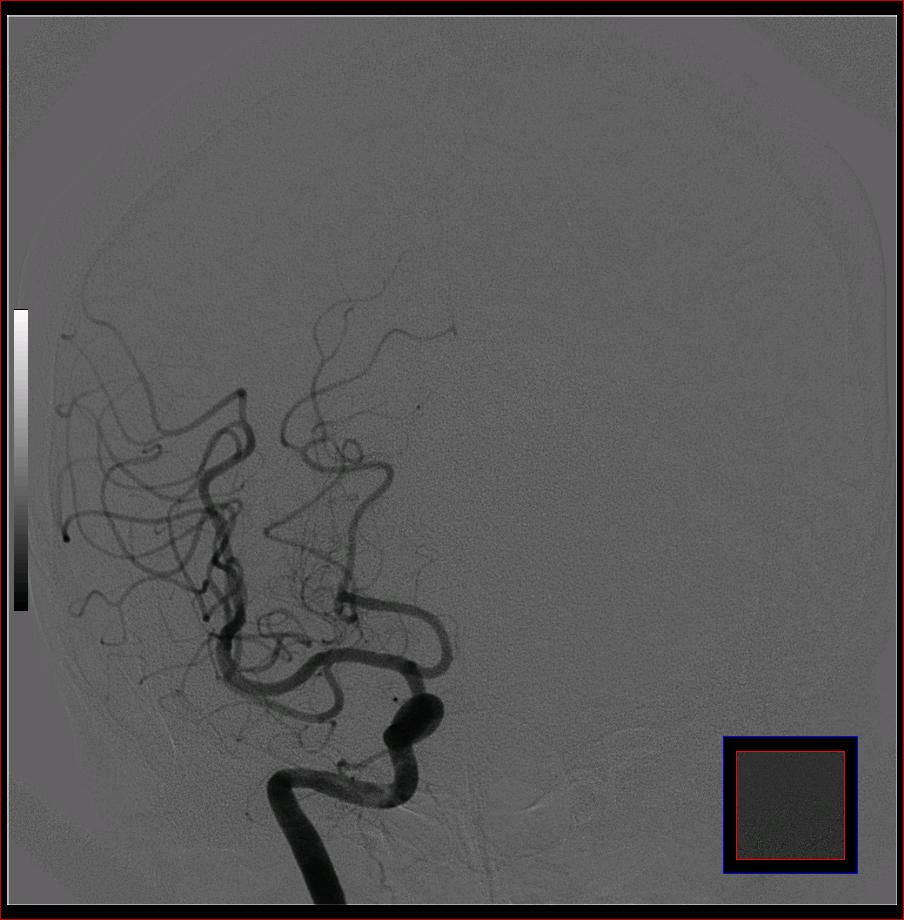

标题: DSA0121:脑血管造影

男,65岁,肢体无力。

左侧大脑中动脉水平段狭窄.

右侧大脑前a缺如.左侧大脑中动脉m1段狭窄,远端分支分布稀疏.

前交通或稍远端动脉瘤要仔细查,左大脑中动脉狭窄要鉴别,有可能是痉挛,因为造影导管插得稍深啦。其它就是供血动脉变异较大

烟雾病